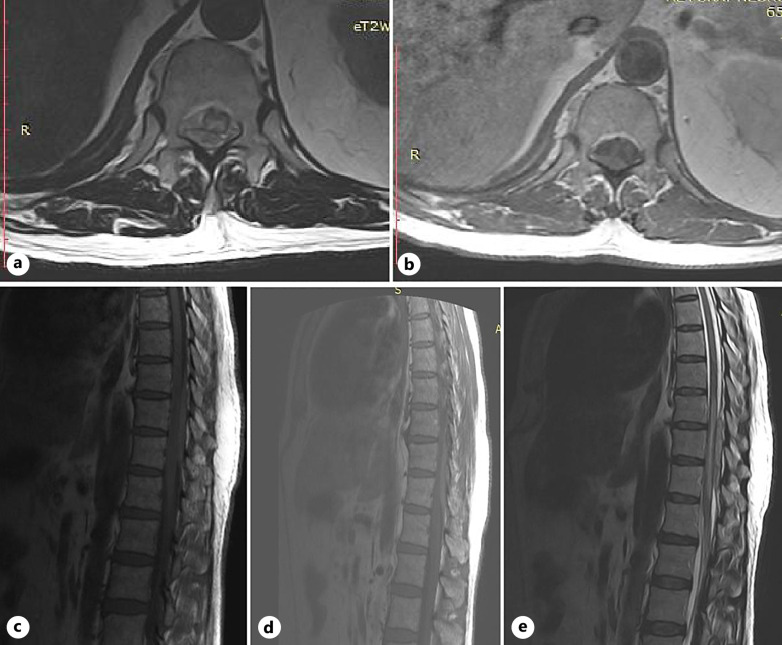

Case presentation: A 55-year-old male was presented with sudden onset of areflexic paraparesis, urinary retention, loss of all sensations below twelve spinal thoracic segments, and severe back pain. This condition necessitated an immediate order of a spinal cord MRI followed by an urgent surgery, which was crucial to save the spinal cord. COVID-19 was confirmed by a positive reverse-transcription-polymerase chain reaction and spinal MRI showed SSDH.